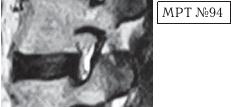

На МРТ № 94 наблюдается позвоночно-двигательный сегмент в стадии развития дегенерации. Высота межпозвонкового диска ещё сохранена, однако уже наблюдается разрушение пульпозного ядра, нарушение гидратации и так далее. В общем, явные признаки развития дегенеративно-дистрофического процесса. Конгруэнтность дугоотростчатого сустава пока ещё не нарушена, суставная капсула визуально целая, но с явными признаками травматизации за счёт перерастяжения. Несмотря на такую травматизацию, вследствие нестабильности, выраженную дегенерацию, человек не чувствует боли из-за работы вышеупомянутых рецепторов в дугоотростчатом суставе, благодаря сигналам которых запускается механизм выработки эндогенных опиатных пептидов. То есть, получается своеобразный феномен: наблюдается постоянная травматизация, а боли человек не чувствует.

Однако когда, к примеру, речь идёт не только о травматизации дугоотростчатого сустава за счёт перерастяжения суставной капсулы, а о стенозе фораминальных отверстий с ущемлением спинномозгового корешка, то здесь уже пациент чувствует явную боль, поскольку организм не справляется с данной ситуацией. Своей «болью», в качестве сигнала «тревоги», он «даёт знать» человеку о наличии серьёзной проблемы.